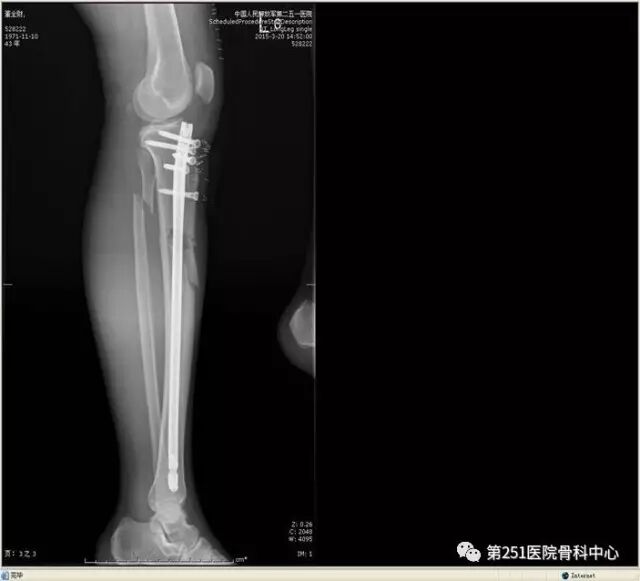

病例4:女性,车祸伤,同侧股骨、股骨颈合并胫腓骨骨折。

![]()